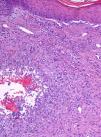

Forty months later the patient developed four reddish, nodular skin lesions on the lower left leg (Fig. 4). A biopsy of one of these lesions was performed, and histopathology revealed suppurative, granulomatous inflammation in the dermis. Grocott’ methenamine silver nitrate staining showed diffusely distributed fungal elements (Fig. 5). Samples were subcultured on Sabouraud dextrose agar and produced fast-growing, fungal colonies with an olive-green undersurface. Direct species differentiation was hampered by the absence of conidia, and so molecular techniques were used. DNA was extracted from the biopsy and the Internal Transcribed Spacer (ITS) 1–2 region, which includes the 5.8S ribosomal DNA gene, was amplified using universal primers ITS1-4.4 The sequence obtained (552 base pairs) was compared with those in the GenBank DNA database (www.ncbi.nlm.nih.gov). This sequence showed 98% homology with a strain of A. triticina. The colonies were then transferred to Czapek agar (Difco) and analyzed by microscope, which revealed oval, brown conidia with horizontal and longitudinal septa.